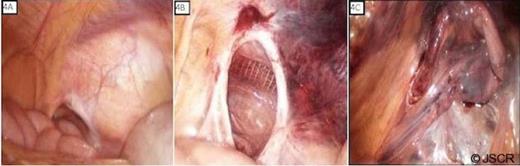

Diagnostic trans-abdominal laparoscopy was performed to evaluate the intestines, define the hernia defect anatomy, and attempt hernia reduction. Exploration revealed normal appearing bowel and a large right sided indirect hernia defect and the hernia contents were reduced without undue difficulty (Figure 4).

The trans-abdominal laparoscopic ports were left in position and additional laparoscopic ports place for a totally extraperitoneal approach for repair. After adequate dissection of the preperitoneal space and reduction of the hernia sac, a 15cm X 15cm polyester mesh was used to broadly cover the direct, indirect and femoral spaces. The laparoscope was then reinserted transabdominally to ensure wide mesh overlap of the defect (Figure 5).

There was a large redundant hernia sac with a wide opening, worrisome for potential internal herniation of abdominal contents; the hernia sac was folded over itself and tacked to the abdominal wall, above the level of the anterior superior iliac spine, to prevent this risk. The patient had an uneventful post-operative recovery and there is no evidence of recurrence 12 months post-repair.